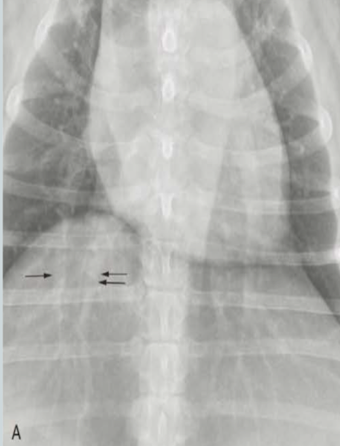

What are the arrows pointing to? Pattern?

Lobar signs

alveolar pattern

Pattern?

Structured interstitial pattern